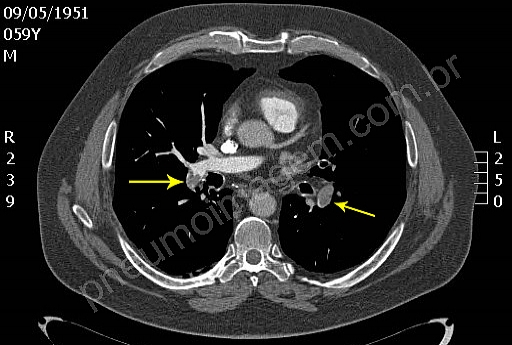

Veja imagens sobre embolia pulmonar no PneumoImagem, clique aqui.